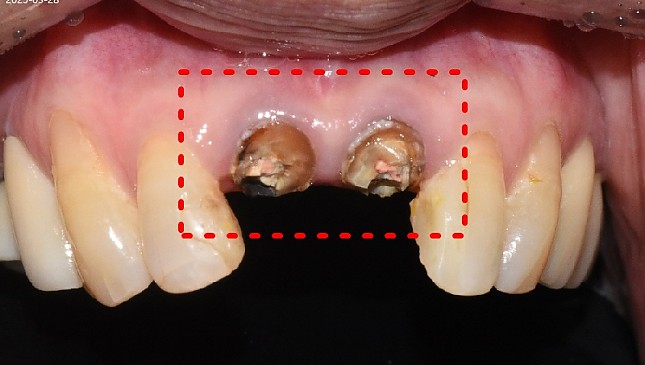

치아살리기 치료 전후 사진

치아살리기의 압도적 결과는 헌신하는 의료진의 결실입니다.

잇몸 전체가 무너져 동시다발적으로 죽어가던 치아들을 한꺼번에 살려 냅니다.